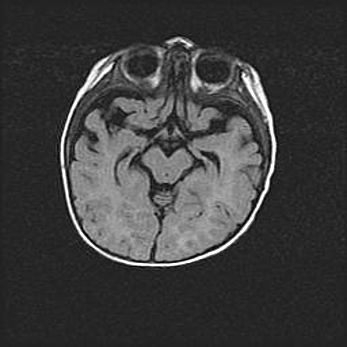

Церебральная ишемия II.

Возраст: 5 дней

Вес: 3400 г

Пол: женский

Окружность головы: 35 см

Срок гестации: 39 недель

Церебральная ишемия – это заболевание, характеризующееся недостаточностью (гипоксией) либо полным прекращением (аноксией) снабжения мозга кислородом по причине закупорки одного или нескольких сосудов. Это приводит к  что метаболическим расстройствам различной степени тяжести в тканях головного мозга, развитию коагуляционных некрозов и гибели нейронов.